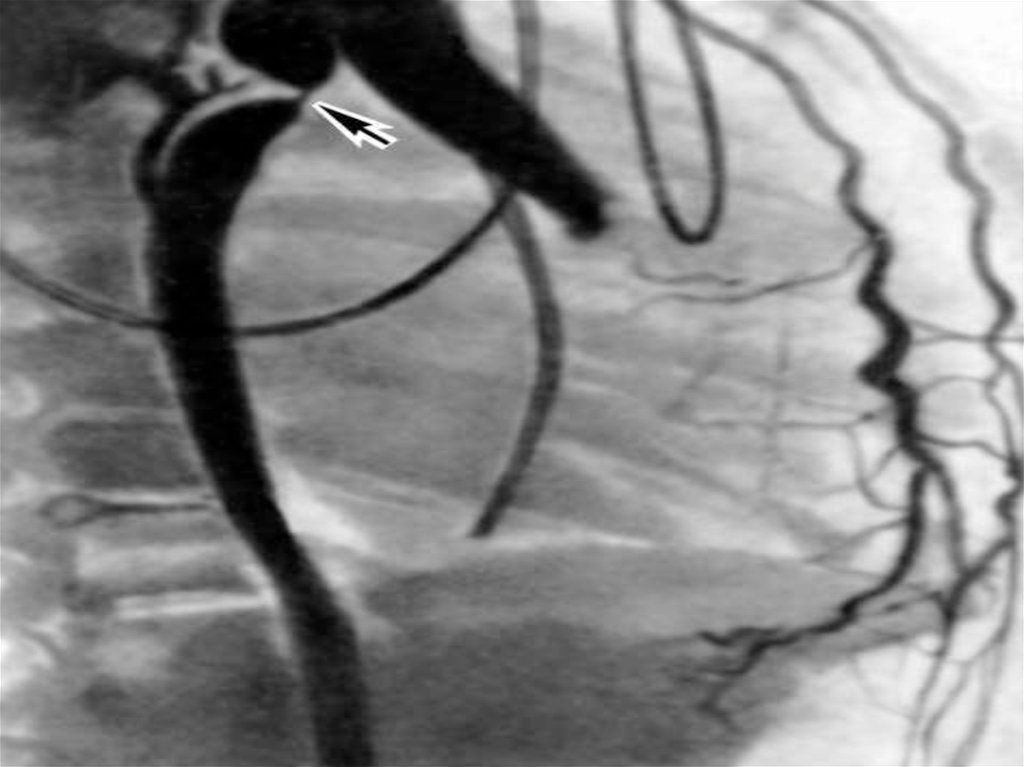

1. Аорта коартациясы:

Аортаның даму

кемістігінен жергілікті

тарылуы.

Коартация , доғаның мойнағы мен

бифуркация аралығының кез келген

жерінде орналасуы мүмкін, бірақ ең

жиі доға мойнағында орналасады. Бұл

ақау туа біткен жүрек ақауларындың

15-18% құрайды.